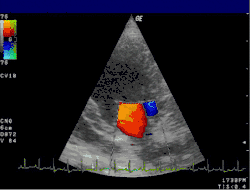

Цветовое доплеровское картирование (ЦДК)